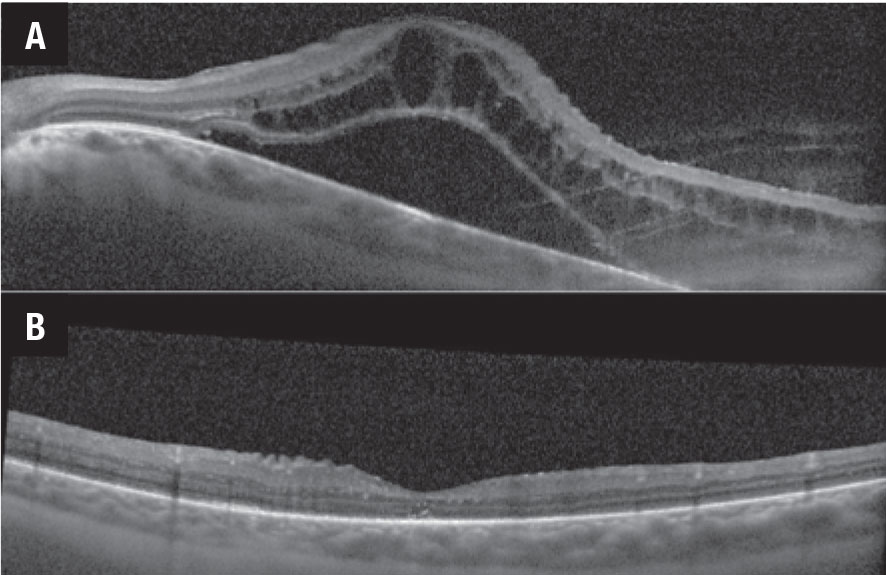

Figure 2. Optical coherence tomography scans demonstrate macular edema before (A) and after (B) intravenous tocilizumab therapy. |

The APTITUDE trial evaluating tocilizumab in TNFi-refractory JIA uveitis failed to meet its primary endpoint of inflammatory control, although about 30 percent of patients showed improvement when switched from a TNFi to tocilizumab.11 Tocilizumab does appear to be effective for the treatment of retinal vascular leakage, with 83 percent of patients showing improvement in angiographic inflammation (Figure 1).12 Tocilizumab has also proven to be highly effective in the treatment of uveitic macular edema, with early studies showing a dramatic response to treatment (Figure 2).13